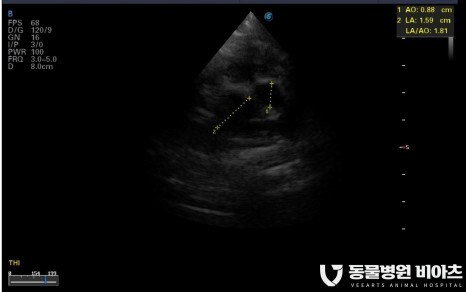

4. 엑스레이/초음파

초음파(LA:Ao, LVIDDN)

심장 초음파

심장 초음파는

심장 내강의 크기

심장벽 두께(LA:AO),

판막 모양의 이상 여부

혈관의 비정상적 확장 여부 등

엑스레이로는 확인이 어려운

심장 구조 변화의 많은 부분을 확인할 수 있습니다.